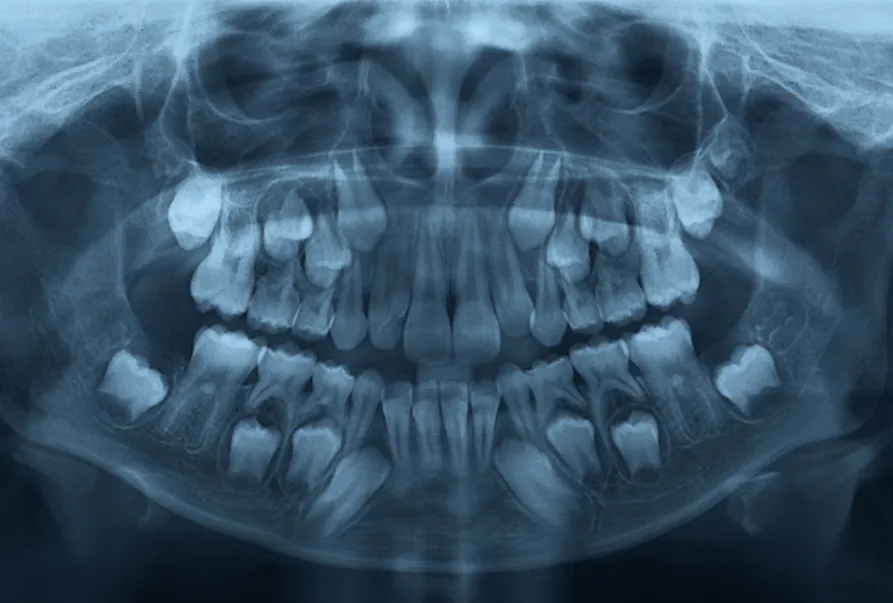

Dental diagnosis and X-ray imaging form the foundation of exceptional oral healthcare at Symphony Dental Clinic, your trusted dentist in Bandra West. It allows us to see what’s invisible to the naked eye—hidden cavities between teeth, bone loss from gum disease, infections at tooth roots, impacted wisdom teeth, jaw abnormalities, and even early signs of oral cancer. This comprehensive approach ensures nothing is overlooked, giving you complete peace of mind about your dental health.

At our dental clinic in Khar West, we utilize state-of-the-art digital X-ray technology that provides crystal-clear images of your teeth, jaw, and surrounding structures. Unlike traditional film X-rays, our digital imaging system delivers instant results with up to 90% less radiation exposure, making it safer for patients of all ages. As the best dentist in Bandra, Dr. Sailee Kalyankar and her team believe that accurate diagnosis is the cornerstone of effective treatment planning and long-term oral health.

Digital X⎯Ray Imaging

imaging. We may take Bitewing X-rays, Periapical X-rays & Panoramic X-rays